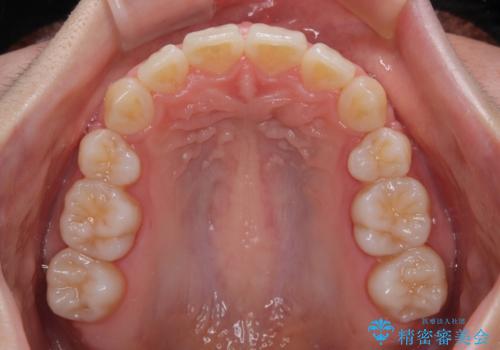

深い咬み合わせの改善に時間がかかりましたが、下顎前歯がしっかりと見えるまでに整えることができ、口元の突出感も大幅に改善することができました。